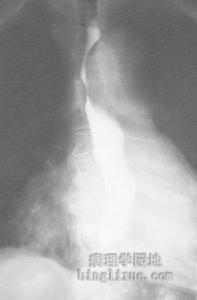

2.腹部X線平片常有腸黏膜增厚、小腸脹氣,部分腸麻痹病人表現為腸梗阻。鋇灌腸可能發現腸管邊呈毛刷狀、指壓跡症和散在的圓形、不規則形充盈缺損。氣鋇雙重造影可提供更多的診斷指標,但必須小心操作防止腸穿孔的發生。